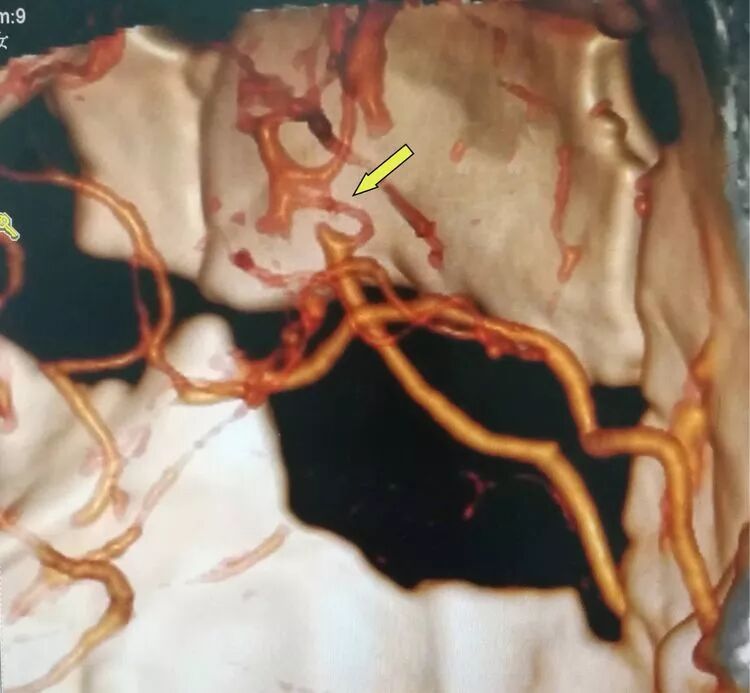

箭头所示为颞浅动脉(供血动脉)与左侧大脑中动脉M4段(受体)经精密的缝合吻合到一起。

患者术后1个个月和3个月分别复查CTA及DSA见血管吻合确切,血流通畅。